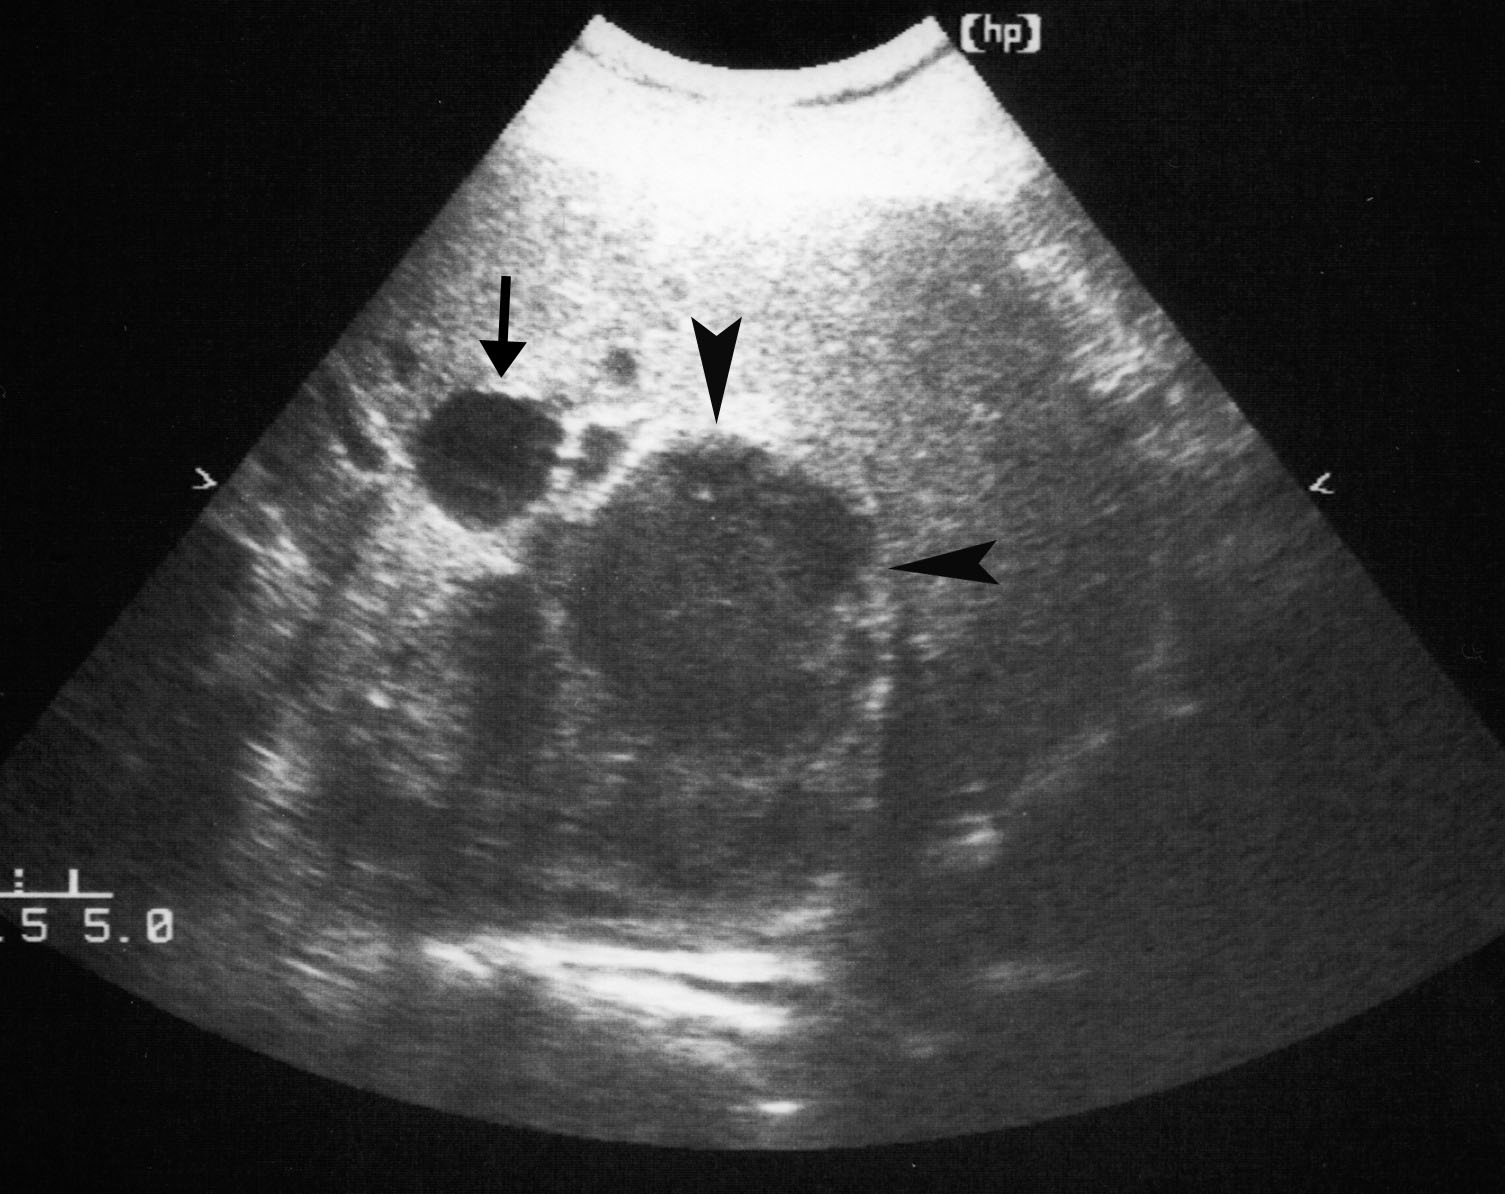

Even though Gemella morbillorum infection (GMI) is rare in humans, it may, nevertheless, cause endocarditis, meningitis, brain abscess, pleural empyema, nephritis, mediastinitis, and – occasionally – liver abscess. We are describing the case of a 64-year-old Caucasian male admitted with fever and abdominal pain. Laboratory parameters revealed inflammation signs, and instrumental examinations showed the presence of diverticula in the ascending colon. Abdominal ultrasound (US) and computer tomography (CT) showed two focal lesions in the right liver lobe. One had the characteristics of a simple cyst; the second was hypoechoic with a low density area, possibly containing necrotic material. US-guided needle biopsy was found negative for neoplastic cells, showing purulent infiltrate. Pus culture was found positive for GMI. Systemic antibiotic therapy, coupled with repeated US-guided needle aspiration, induced the resolution of the hepatic abscess. Few cases have been reported of hepatic abscess caused by GMI in immunocompetent non-cirrhotic subjects.Authors